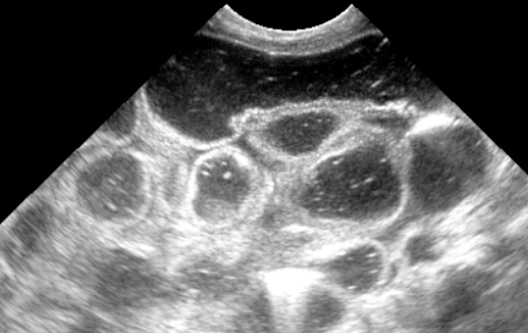

Caracterizada por un engrosamiento anormal del músculo pilórico, lo que lleva a una obstrucción de la salida gástrica. Esta condición es una causa común de vómitos no biliosos en lactantes y generalmente se presenta entre las 2 y 12 semanas de vida.

El diagnóstico se realiza principalmente mediante ecografía, que muestra un alargamiento constante y un engrosamiento de la pared del píloro, con una longitud del canal pilórico superior a 18 mm y un grosor muscular de al menos 4 mm.

Ejemplos de estenosis pilorica hipertrofica infantil.